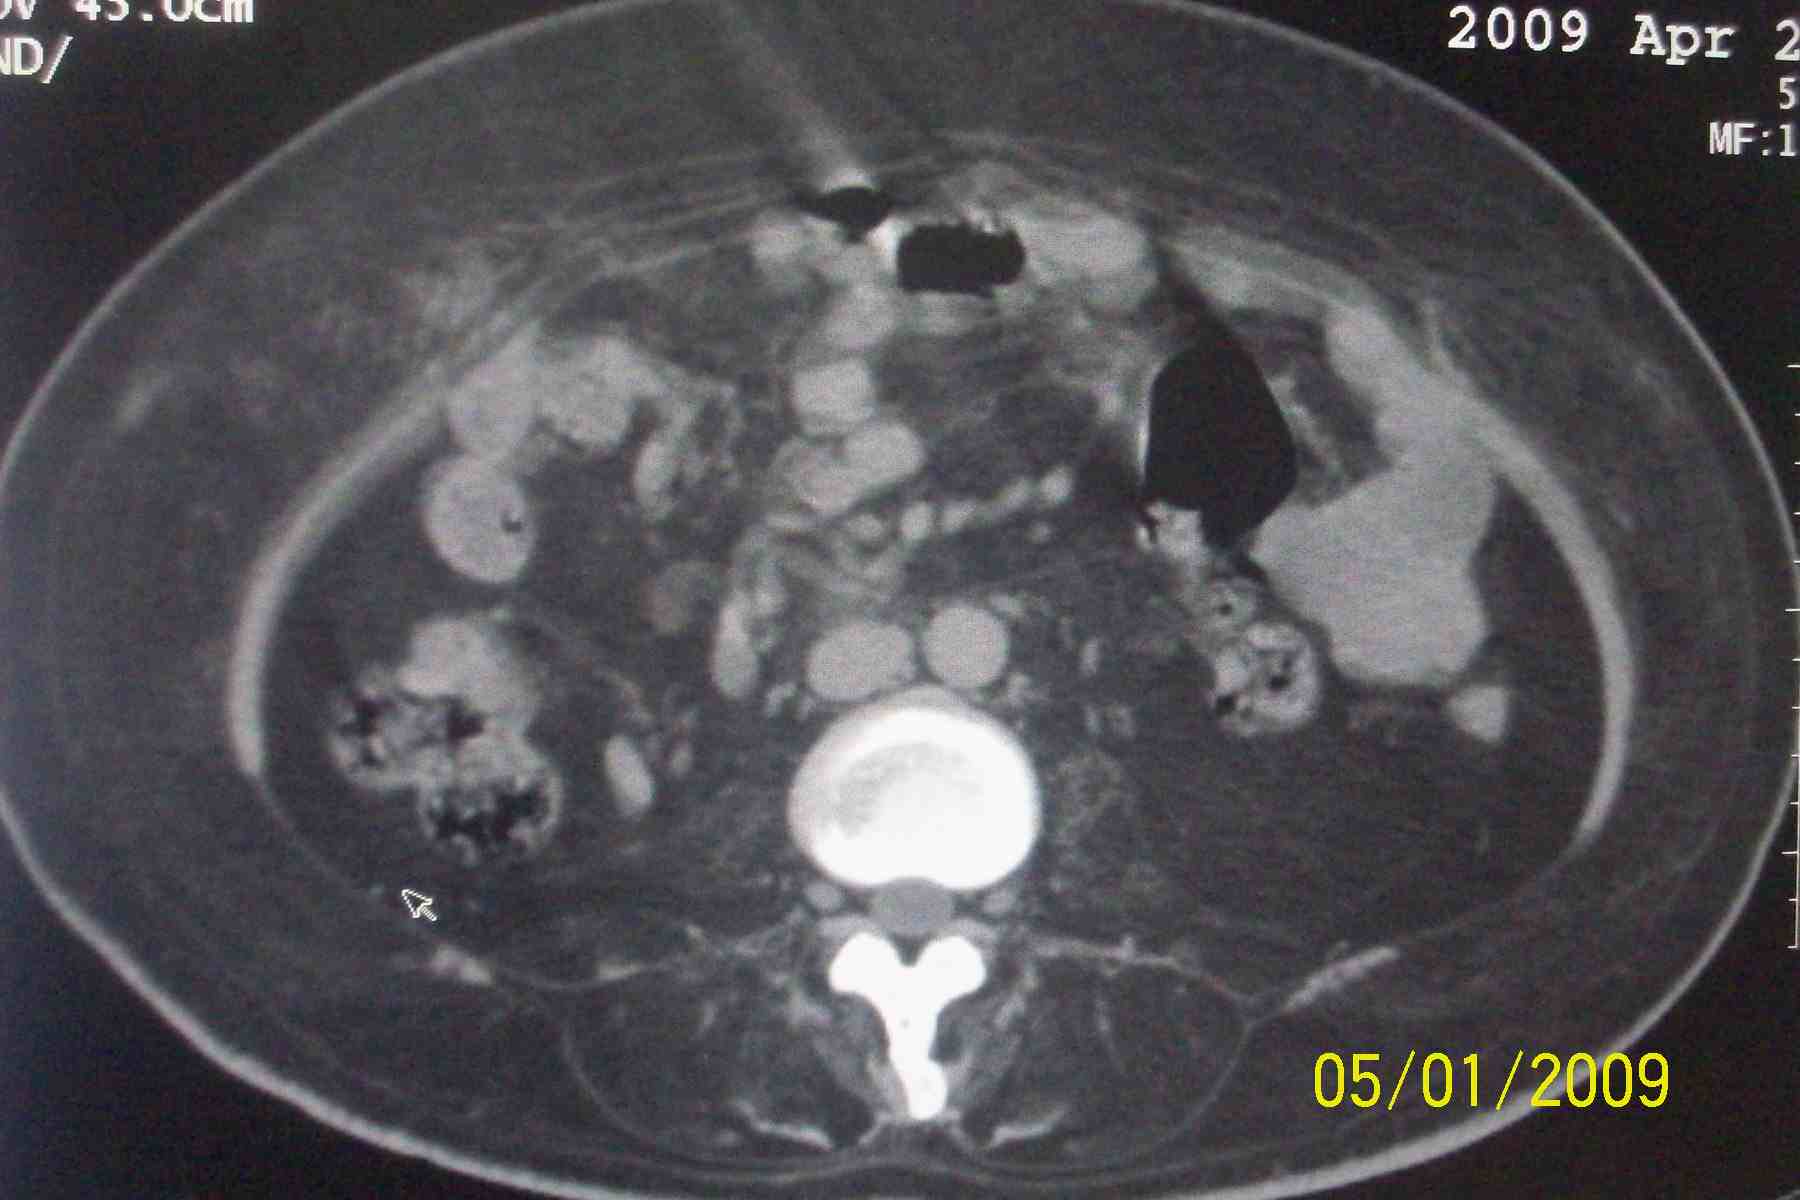

以下是引用杀毒软件在2009-5-1 17:43:00的发言:[br]良性对称性脂肪增多症

以下是引用ncy888888在2009-5-1 17:39:00的发言:[br]肾怎么弄丢了一个。